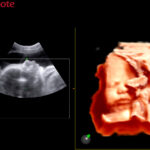

- XSTIC programos pagalba gaunama vaisiaus širdies ertmių spalvinė ir galios rekonstrukcija

- XLight funkcija, kurios pažangus algoritmas pagerina tūrinę vaizdų atkūrimo kokybę